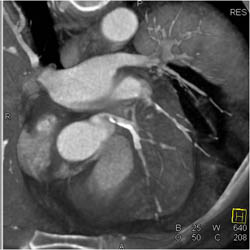

Sliding MIP of Normal LAD